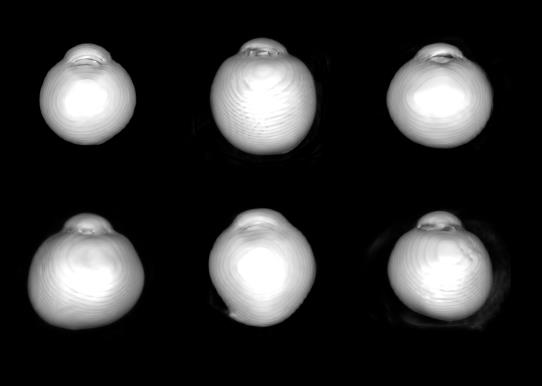

▲3D-MRI조사 안구의 다양한 3차원적 형태. / 사진 = 보라매병원 제공

안구는 흔히 공 모양으로 그려지지만 사실 완벽한 구형은 아니다.

안구는 성장하는 과정에서 여러 방향으로 팽창하는데, 이로 인해 앞뒤로 긴 형태, 좌우로 긴 형태, 그리고 비대칭적으로 돌출된 형태에 이르기까지 다양한 형태를 가진다.

보라매병원 안과 김석환 교수팀은 #3D-MRI 분석을 통해 이 같은 안구의 3차원적 형태가 신경의 형태와 밀접한 관계를 갖는다는 사실을 세계 최초로 입증했다.